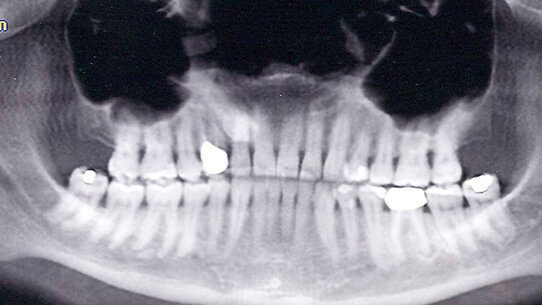

L’eziologia delle patie disfunzionali è altrettanto complessa e talvolta controversa; infatti, si possono osservare soggetti affetti da sintomi similari, tra i quali alcuni soffrono di un deterioramento dell’articolazione temporo-mandibolare (Figg. 2a, 2b), altri non presentano modificazioni degenerative dell’ATM. La causa dei TMD è multifattoriale e presenta spesso, oltre a una problematica fisica, componenti come stress, ansia, attacchi di panico. Spesso la complessità diagnostica ed eziologica della problematica disorienta il clinico su quale trattamento scegliere nella gestione della malattia.